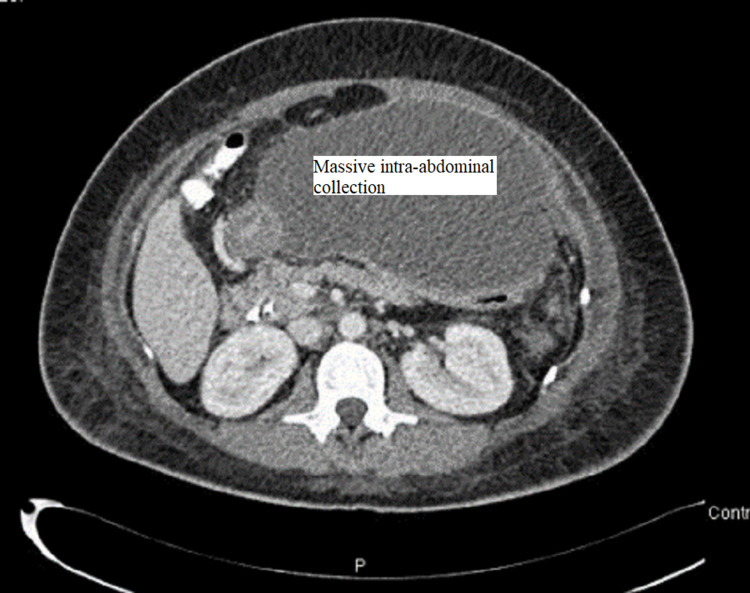

CT abdomen was done and showed a large amount of free fluid in the perihepatic, peri-splenic, and pelvic regions, along with extensive subcutaneous edema and stranding with free air within the right lateral abdominal wall (Figures 3–5). In addition, the CT revealed a mild intrahepatic biliary duct and CBD dilatation.